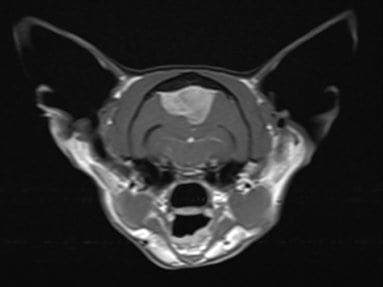

So, Henry was put into the hospital’s state-of-the-art MRI scanner which revealed that he had a large mass pushing on his brain. Specialist interpretation of the MRI images showed that a tumour called a meningioma was the most likely culprit.